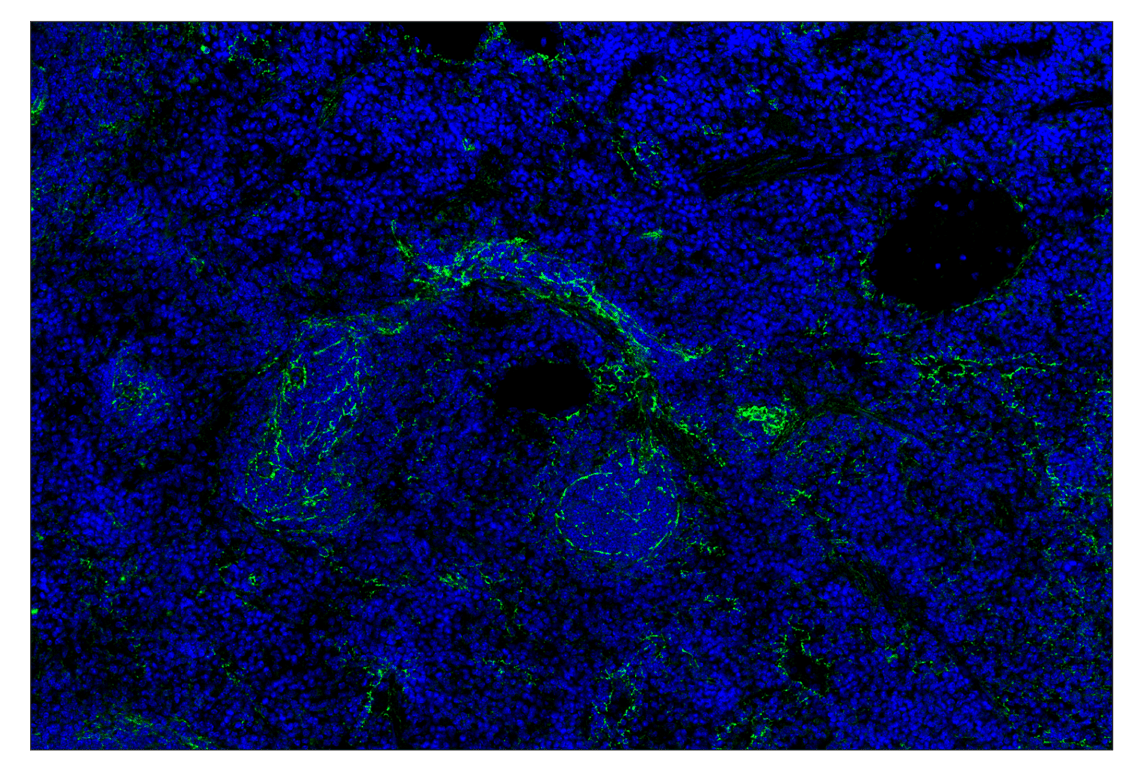

SignalStar™ multiplex immunohistochemical analysis of paraffin-embedded mouse spleen using N-Cadherin (D4R1H) (488; green) and DAPI #4083 (blue).

Immunohistochemistry Image 1: N-Cadherin (D4R1H) & CO-0153-647 SignalStar<sup>™</sup> Oligo-Antibody Pair